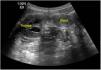

Niña de 11 años con síndrome de Down, que acude a urgencias por presentar dolor abdominal de predomino en fosa ilíaca derecha (FID) y fiebre de 48h de evolución. Entre los antecedentes encontramos enfermedad de Hirschsprung tratada mediante colostomía en el período neonatal y posterior descenso abdominoperineal tipo Duhamel, presentando varios episodios de oclusión intestinal posteriores que se resolvieron con tratamiento conservador. A su llegada presentaba regular estado general, fiebre de 39°C, el abdomen era blando y depresible, con dolor intenso y defensa muscular a la palpación de la FID. La analítica sanguínea demostró leucocitosis con neutrofilia y una PCR de 15,5mg/dl. Se realizó ecografía abdominal objetivándose una estructura tubular fija en la FID con paredes engrosadas y contenido líquido (figs. 1 y 2). El estudio se completó con una TAC abdominal confirmándose el diagnóstico de hidropiosalpinx derecho (fig. 3). Se inició antibioterapia endovenosa con amoxicilina-clavulánico objetivándose mejoría clínico-radiológica en las primeras 24h sin precisar drenaje quirúrgico de la colección. Se dio de alta a las 72h con antibioterapia oral y buena evolución posterior.